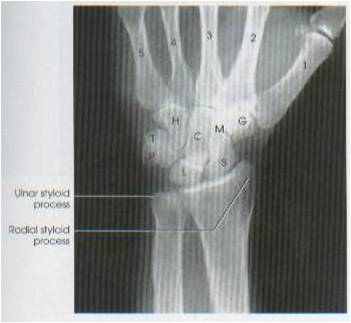

- kriteria radiograf : tampak gambaran metacarpal dan carpal, tampak juga distal ulna dan radius

- soft tissue dan trabecula tulang tampak

- interspace carpallia terlihat jelas

- Kriteria radiograf : tampak tulang-tulang carpalia : navicula, lunatum, triquetrum, pisiform, multangular mayus, multangular minor, capitatum dan hamatum.

- tampak metacarpalia

- tampak 1/3 distal os ulna dan radius

- tampak styloid ulna

- tampak styloid radius

- soft tissue dan trabecula jelas

- densitas radiograf merata